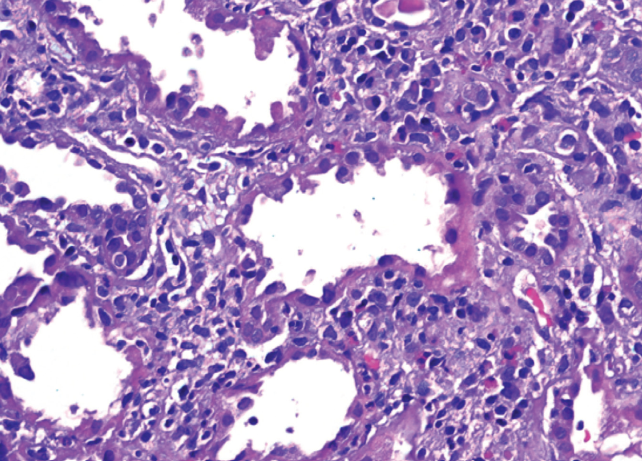

David Effron, MD; Bryan Baskin, DO; Marjorie E. Montanez-Wiscovich, MD, PhD; Stephen Somach, MD

A 37-year-old man presented with a rash of 1-week duration. The rash was pruritic, and erythematous, with involvement of upper extremities, chest, and abdomen.